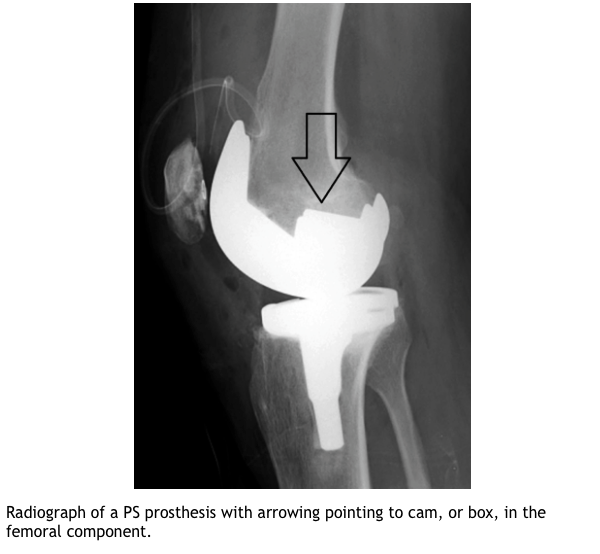

Describe the Posterior stabilised knee replacement?

What are the indications for posterior stabilised TKR?

What are the adv/dis of a posterior stabilised TKR?

ADV

DIS